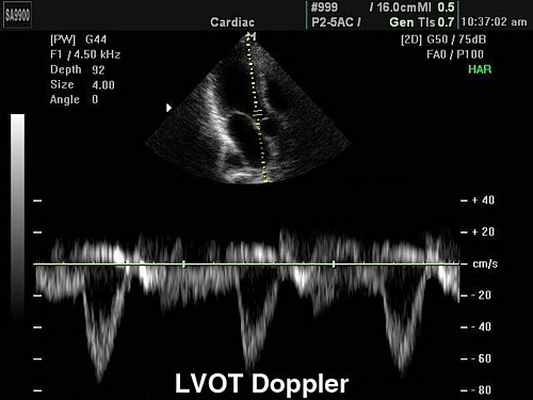

Импульсный допплер (Pulsed Wave, или PW). Графическая разверстка импульсно-волнового допплера отражает характер кровотока в конкретной данной точке, в месте установки контрольного объема. Точка установки контрольного объема называется базовой линией. По вертикали на графике откладывается скорость потока, по горизонтали - время. Все потоки, которые в конкретной данной точке движутся к датчику располагаются на графике выше базовой линии; все потоки, которые движутся от датчика - ниже нулевой линии. Помимо формы и характера кровотока на графике можно зафиксировать щелчки открытия и закрытия створок клапанов, дополнительные сигналы от хорд створок и стенок сердца. Импульсный допплер имеет скоростной предел (не более 2,5 м/с ), поэтому с его помощью нельзя зарегистрировать потоки, имеющие высокую скорость.

Постоянно-волновой допплер (CW - Continuous Wave Doppler). Позволяет регистрировать высокоскоростные потоки. Недостаток метода состоит в том, что на графике регистрируются все потоки по ходу луча. Методика CW допплеровского исследования позволяет произвести расчеты давления в полостях сердца и магистральных сосудов в ту или иную фазу сердечного цикла, рассчитать степень значимости стеноза и т.д.

Основным уравнением CW является уравнение Бернулли, позволяющее расчитать разницу давления или градиент давления.С помощью уравнения можно измерить разницу давления между камерами в норме и при наличии патологического, высокоскоростного кровотока.